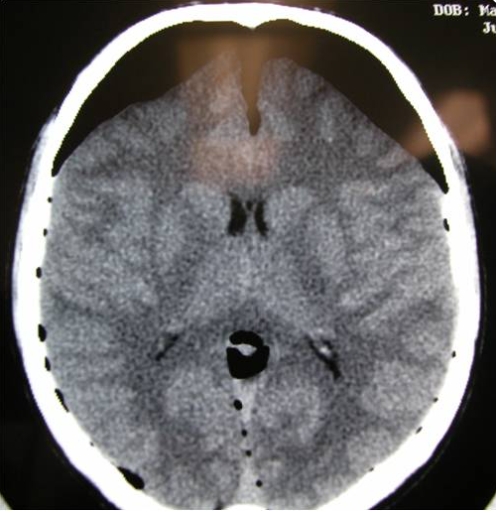

A 21 year-old-man sustained blunt force trauma to his head, had brief loss-of-consciousness and was GCS 15 at initial evaluation, complaining of headaches, nausea and visual disturbance. CT is shown in figures. What is the best management of this patient? Evacuation of hematoma with placement of burr holes Cerebral angiogram and embolization of sinus Place ICP monitor and observe in the ICU Manage conservatively in the ICU with a f/u CT in 6 hrs. Take to the OR emergently for a combined Supra- and infratentorial approach

Take to the OR emergently for a combined Supra- and infratentorial approach